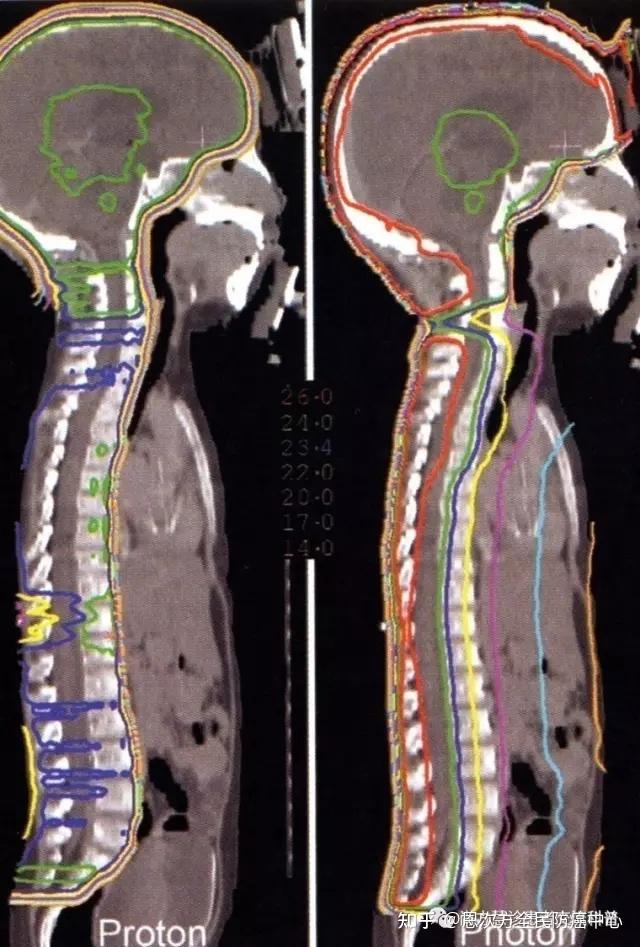

2、质子治疗儿童肿瘤(全脑全脊髓照射):

可以看到,光子放疗时,患者胸腹部正常脏器,接受了不必要的射线照射。因为儿童的生长发育问题,不必要的照射引起的影响较大,质子对比有更多有的优势。这也是日本将儿童的质子治疗纳入国民医保的主要原因。